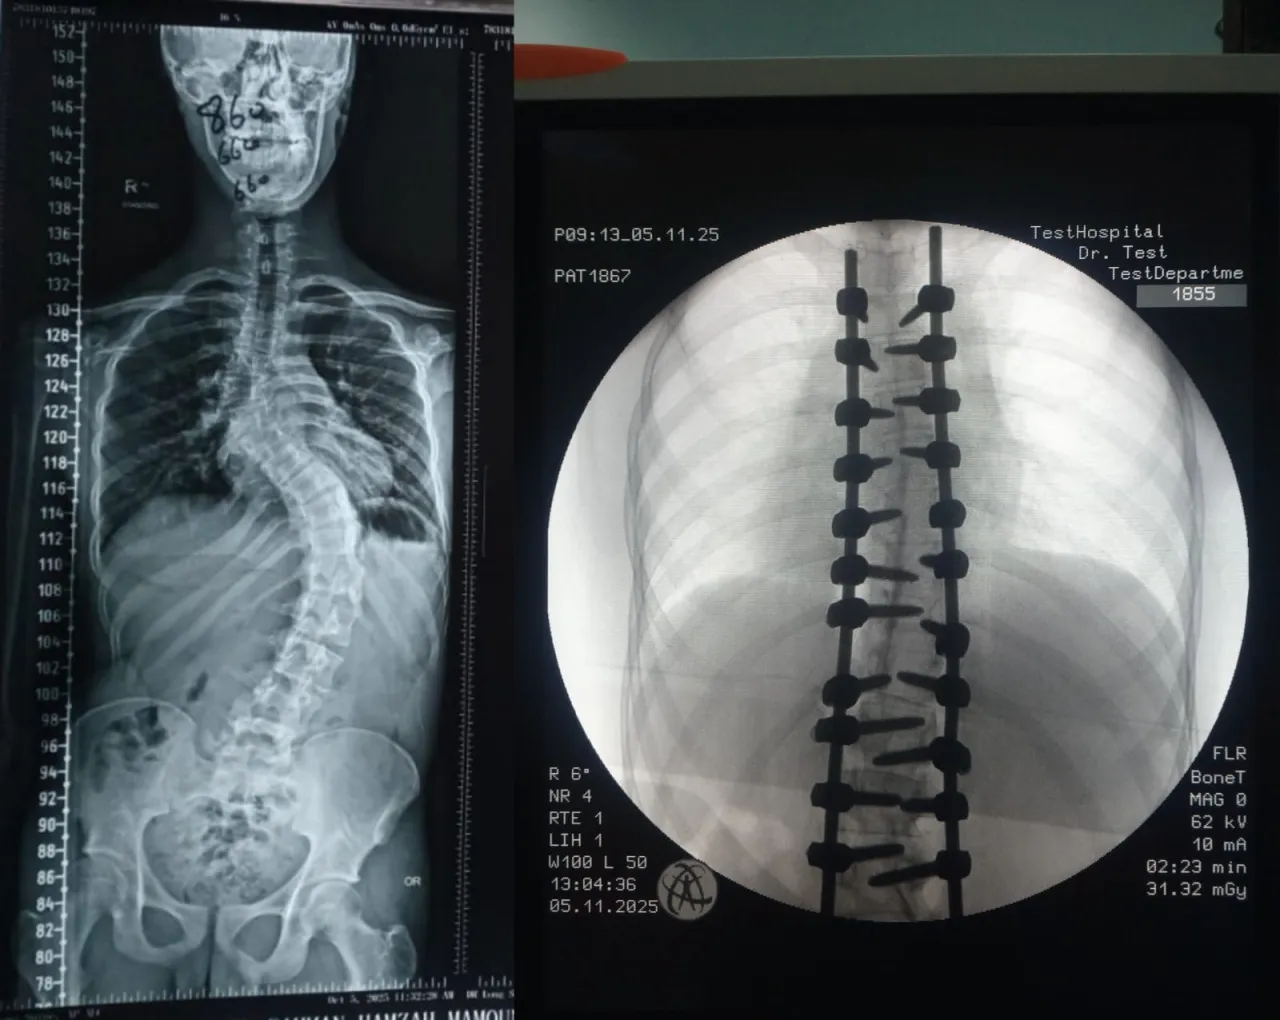

The spinal surgery department at Prince Hamzah Hospital witnessed a distinctive medical achievement represented in a complex surgical intervention to correct scoliosis of the spinal column in one of the patients suffering from severe vertebral deformity.

The operation was performed using advanced surgical navigation equipment, which allowed high precision in dealing with severe structural deformities, and facilitated the guiding of surgical tools within a safe and ideal path.

The operation also included the removal of specific parts of the posterior extremities of the vertebrae to achieve the required correction and restore the natural balance and alignment of the spinal column.